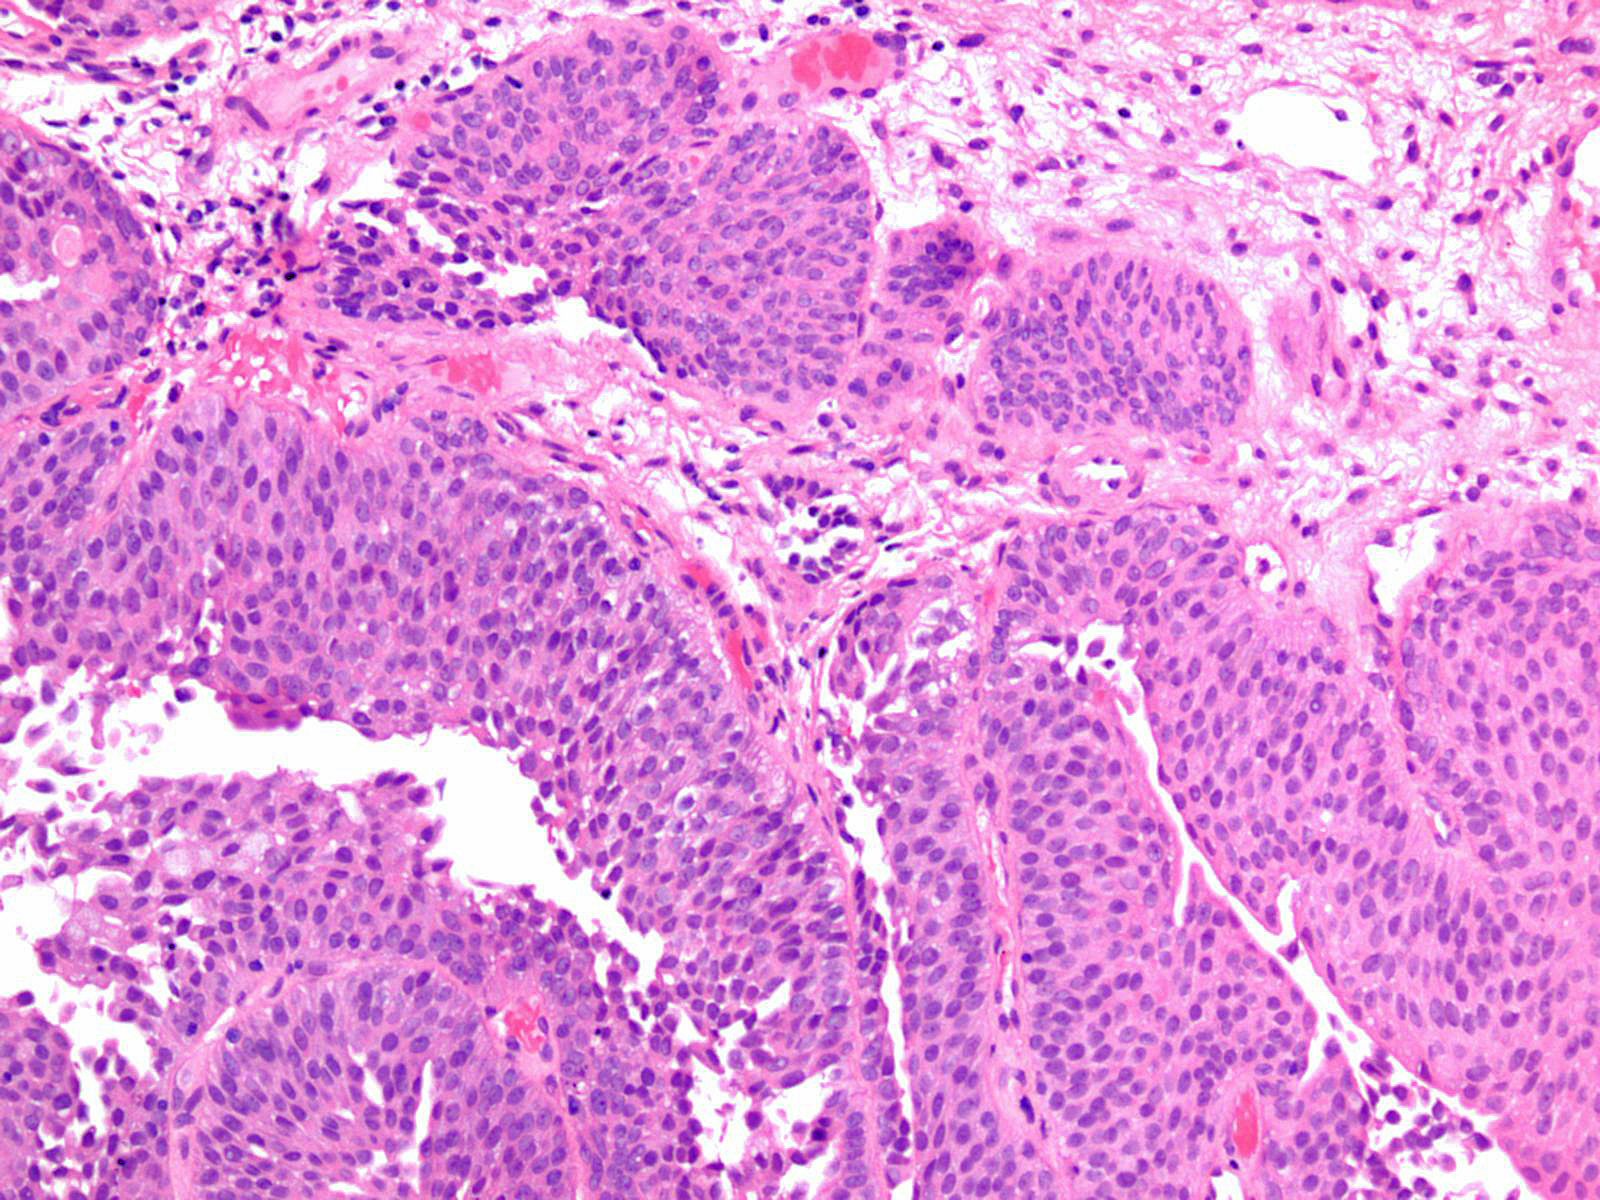

Bladder Papillary Lesions

Case ID: 149

Papilloma

PUNLMP

Low-grade papillary urothelial carcinoma (LG-PUC)

High-grade papillary urothelial carcinoma (HG-PUC)